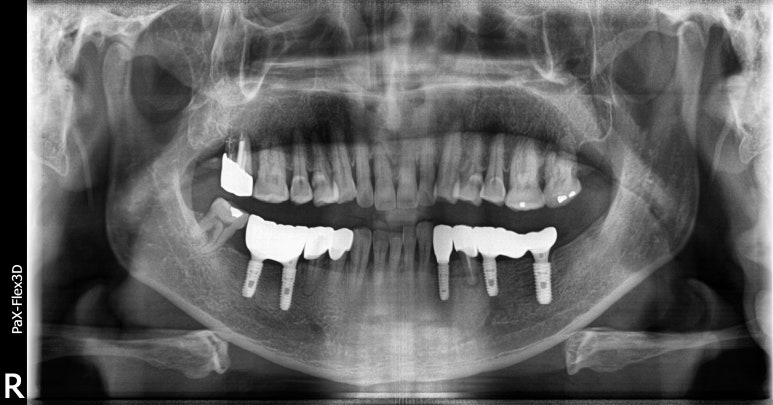

임플란트건강보험 시술 후 엑스레이 사진

2022-08-18

상실되었던 치아들이 임플란트로 빼곡하게 대체된 모습을 확인하실 수 있습니다.

특히 오른쪽 아래(사진상 왼쪽 아래)의 경우 뼈이식 없이 건강보험임플란트를 식립할 수 있었고,

인접한 치아의 크라운까지 교체해 음식을 씹는데 무리가 없으시도록 치료해 드렸습니다.